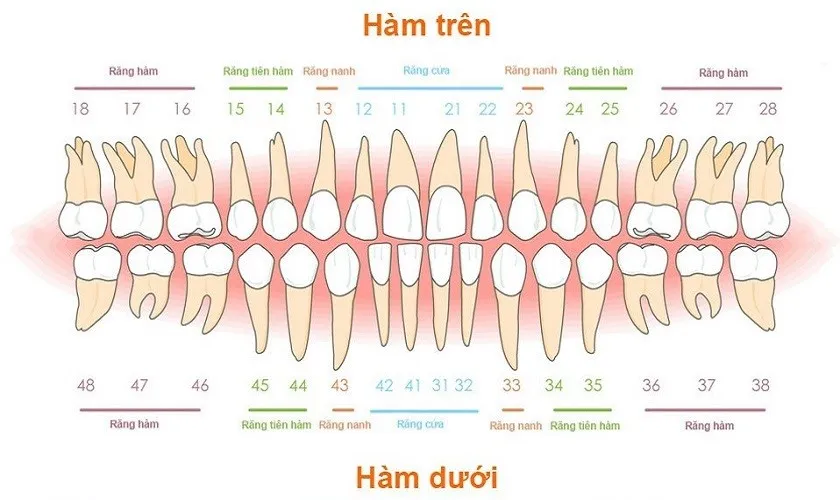

Việc tìm hiểu có mấy răng số 8 là một trong những thắc mắc phổ biến của nhiều người khi bắt đầu quan tâm đến sức khỏe

Việc hiểu rõ có mấy răng hàm trong hàm răng của con người không chỉ giúp bạn có cái nhìn tổng quan về cấu trúc răng miệng